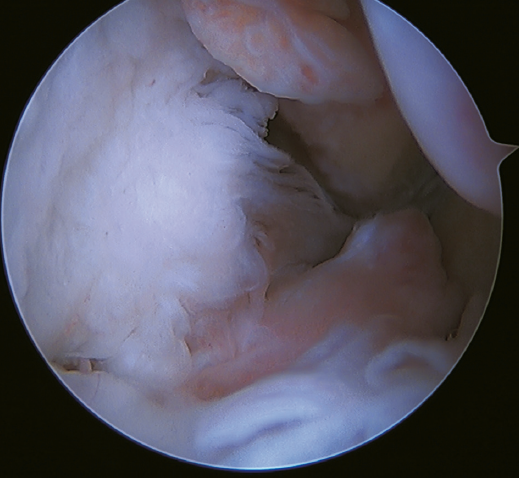

Un reciente consenso(64) recomienda la reconstrucción del LTFA y el LCF (Figuras 5 y 6) en aquellos casos de laxitud generalizada o cuando existe una mala calidad tisular. Otras indicaciones serían cuando existen dudas de la estabilidad subtalar o en aquellos pacientes con rotura del LCF. Para algunos autores, el IMC superior a 30 kg/m2 también sería una indicación para esta técnica.

Figura 5. Rotura del ligamento talofibular anterior y del ligamento calcaneofibular con mala calidad tisular del remanente ligamentoso.